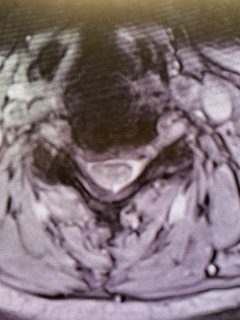

(Fig. 3) AP and Lateral cervical X-ray 6 months from surgery demonstrates a stable construct and alignment.

Postoperatively the patient had an uneventful course with relief of her right arm pain and stable construct (Fig. 3) at follow up at 6 months.